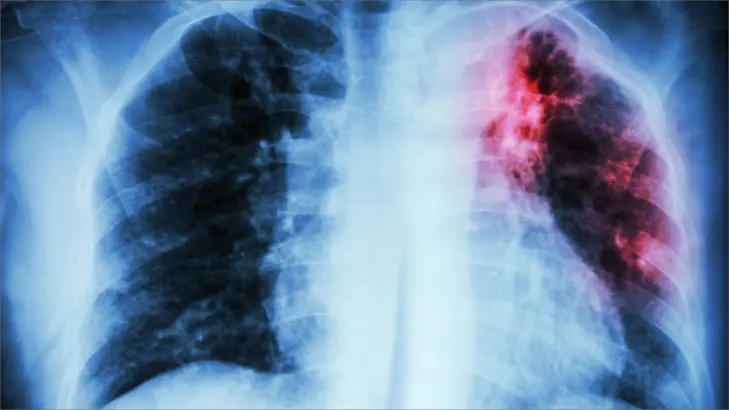

1. الأشعة السينية على الصدر

هي اختبار شائع يُستخدم لتشخيص الالتهاب الرئوي.